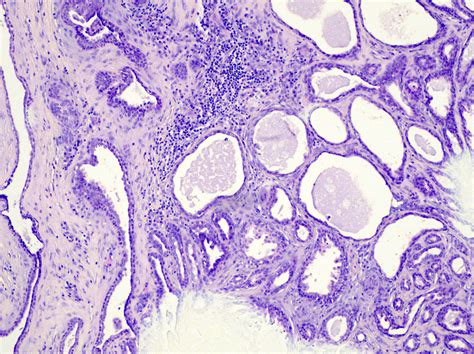

• Biopsy: In some cases, a biopsy may be performed to confirm the diagnosis and rule out malignant tumors. However, biopsies are not always necessary and are typically reserved for cases where the diagnosis is uncertain.